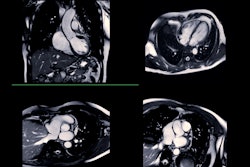

COVID-19 boosts cardiovascular event risk